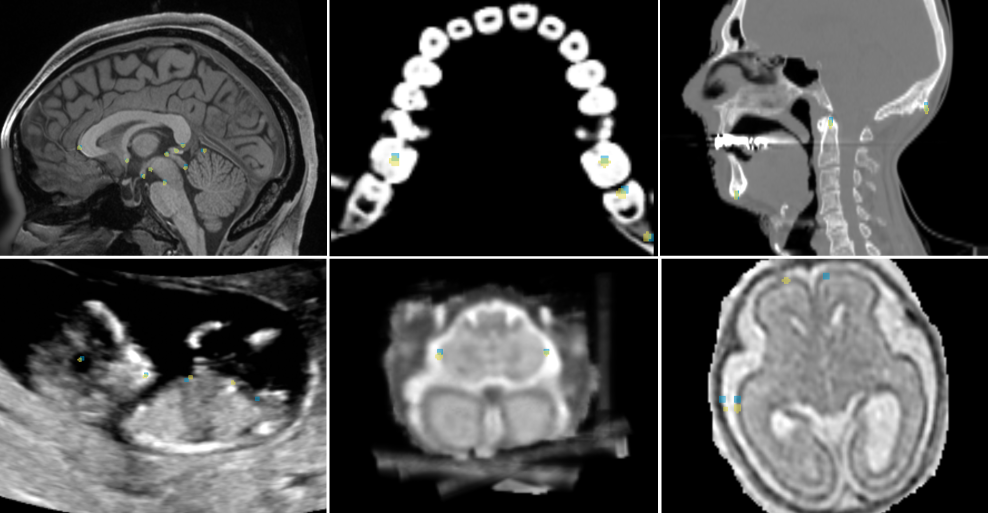

Randomly chosen example predictions for the nnLandmark ResEncM model for all datasets are shown in Figure 9. Visual examples for all methods are given in the Appendix F.